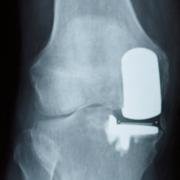

Tibiofemoral UKR.

A unicompartmental knee replacement is a surgical procedure where the surgeon just replaces one part of an arthritic joint.